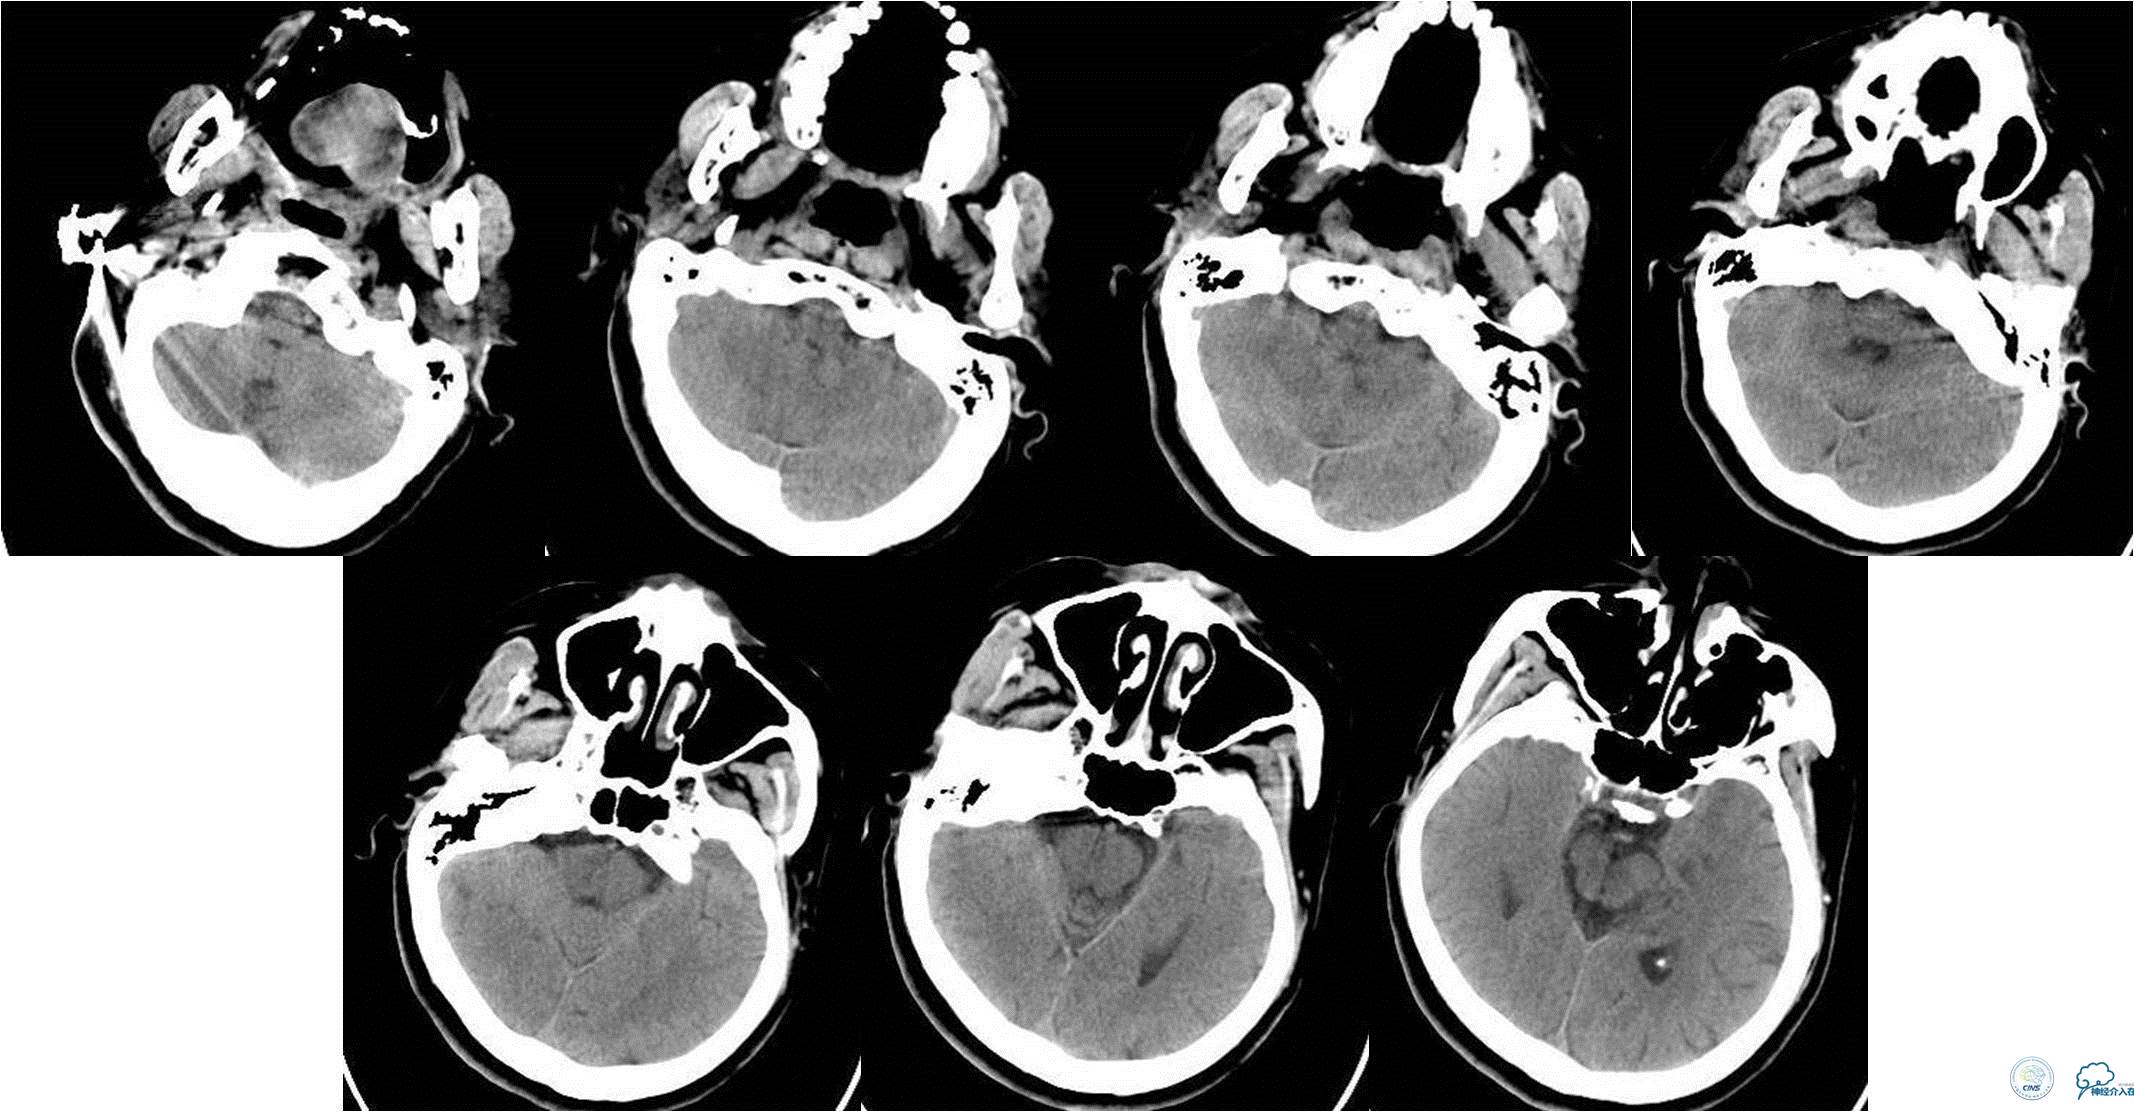

入院时急查颅脑CT(发病2.5小时)

入院时颅脑CTA(发病4小时)